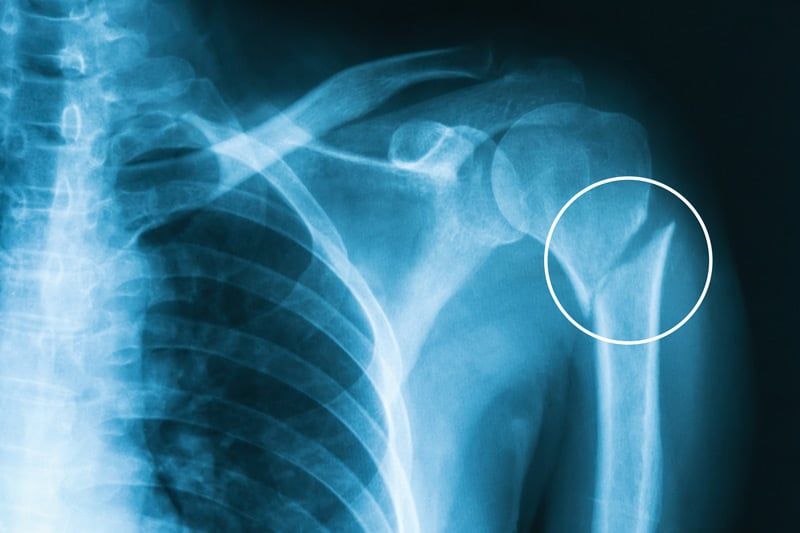

Za diagnozo se uporabljajo rentgenski posnetki (RTG), pri kompleksnejših primerih pa CT ali MRI, ki omogočajo podroben pregled zloma in mehkih tkiv.

Proksimalni zlom nadlahtnice vključuje poškodbe glavice nadlahtnice, kirurškega vratu, anatomskega vratu ali velikega trohantra nadlahtnice.